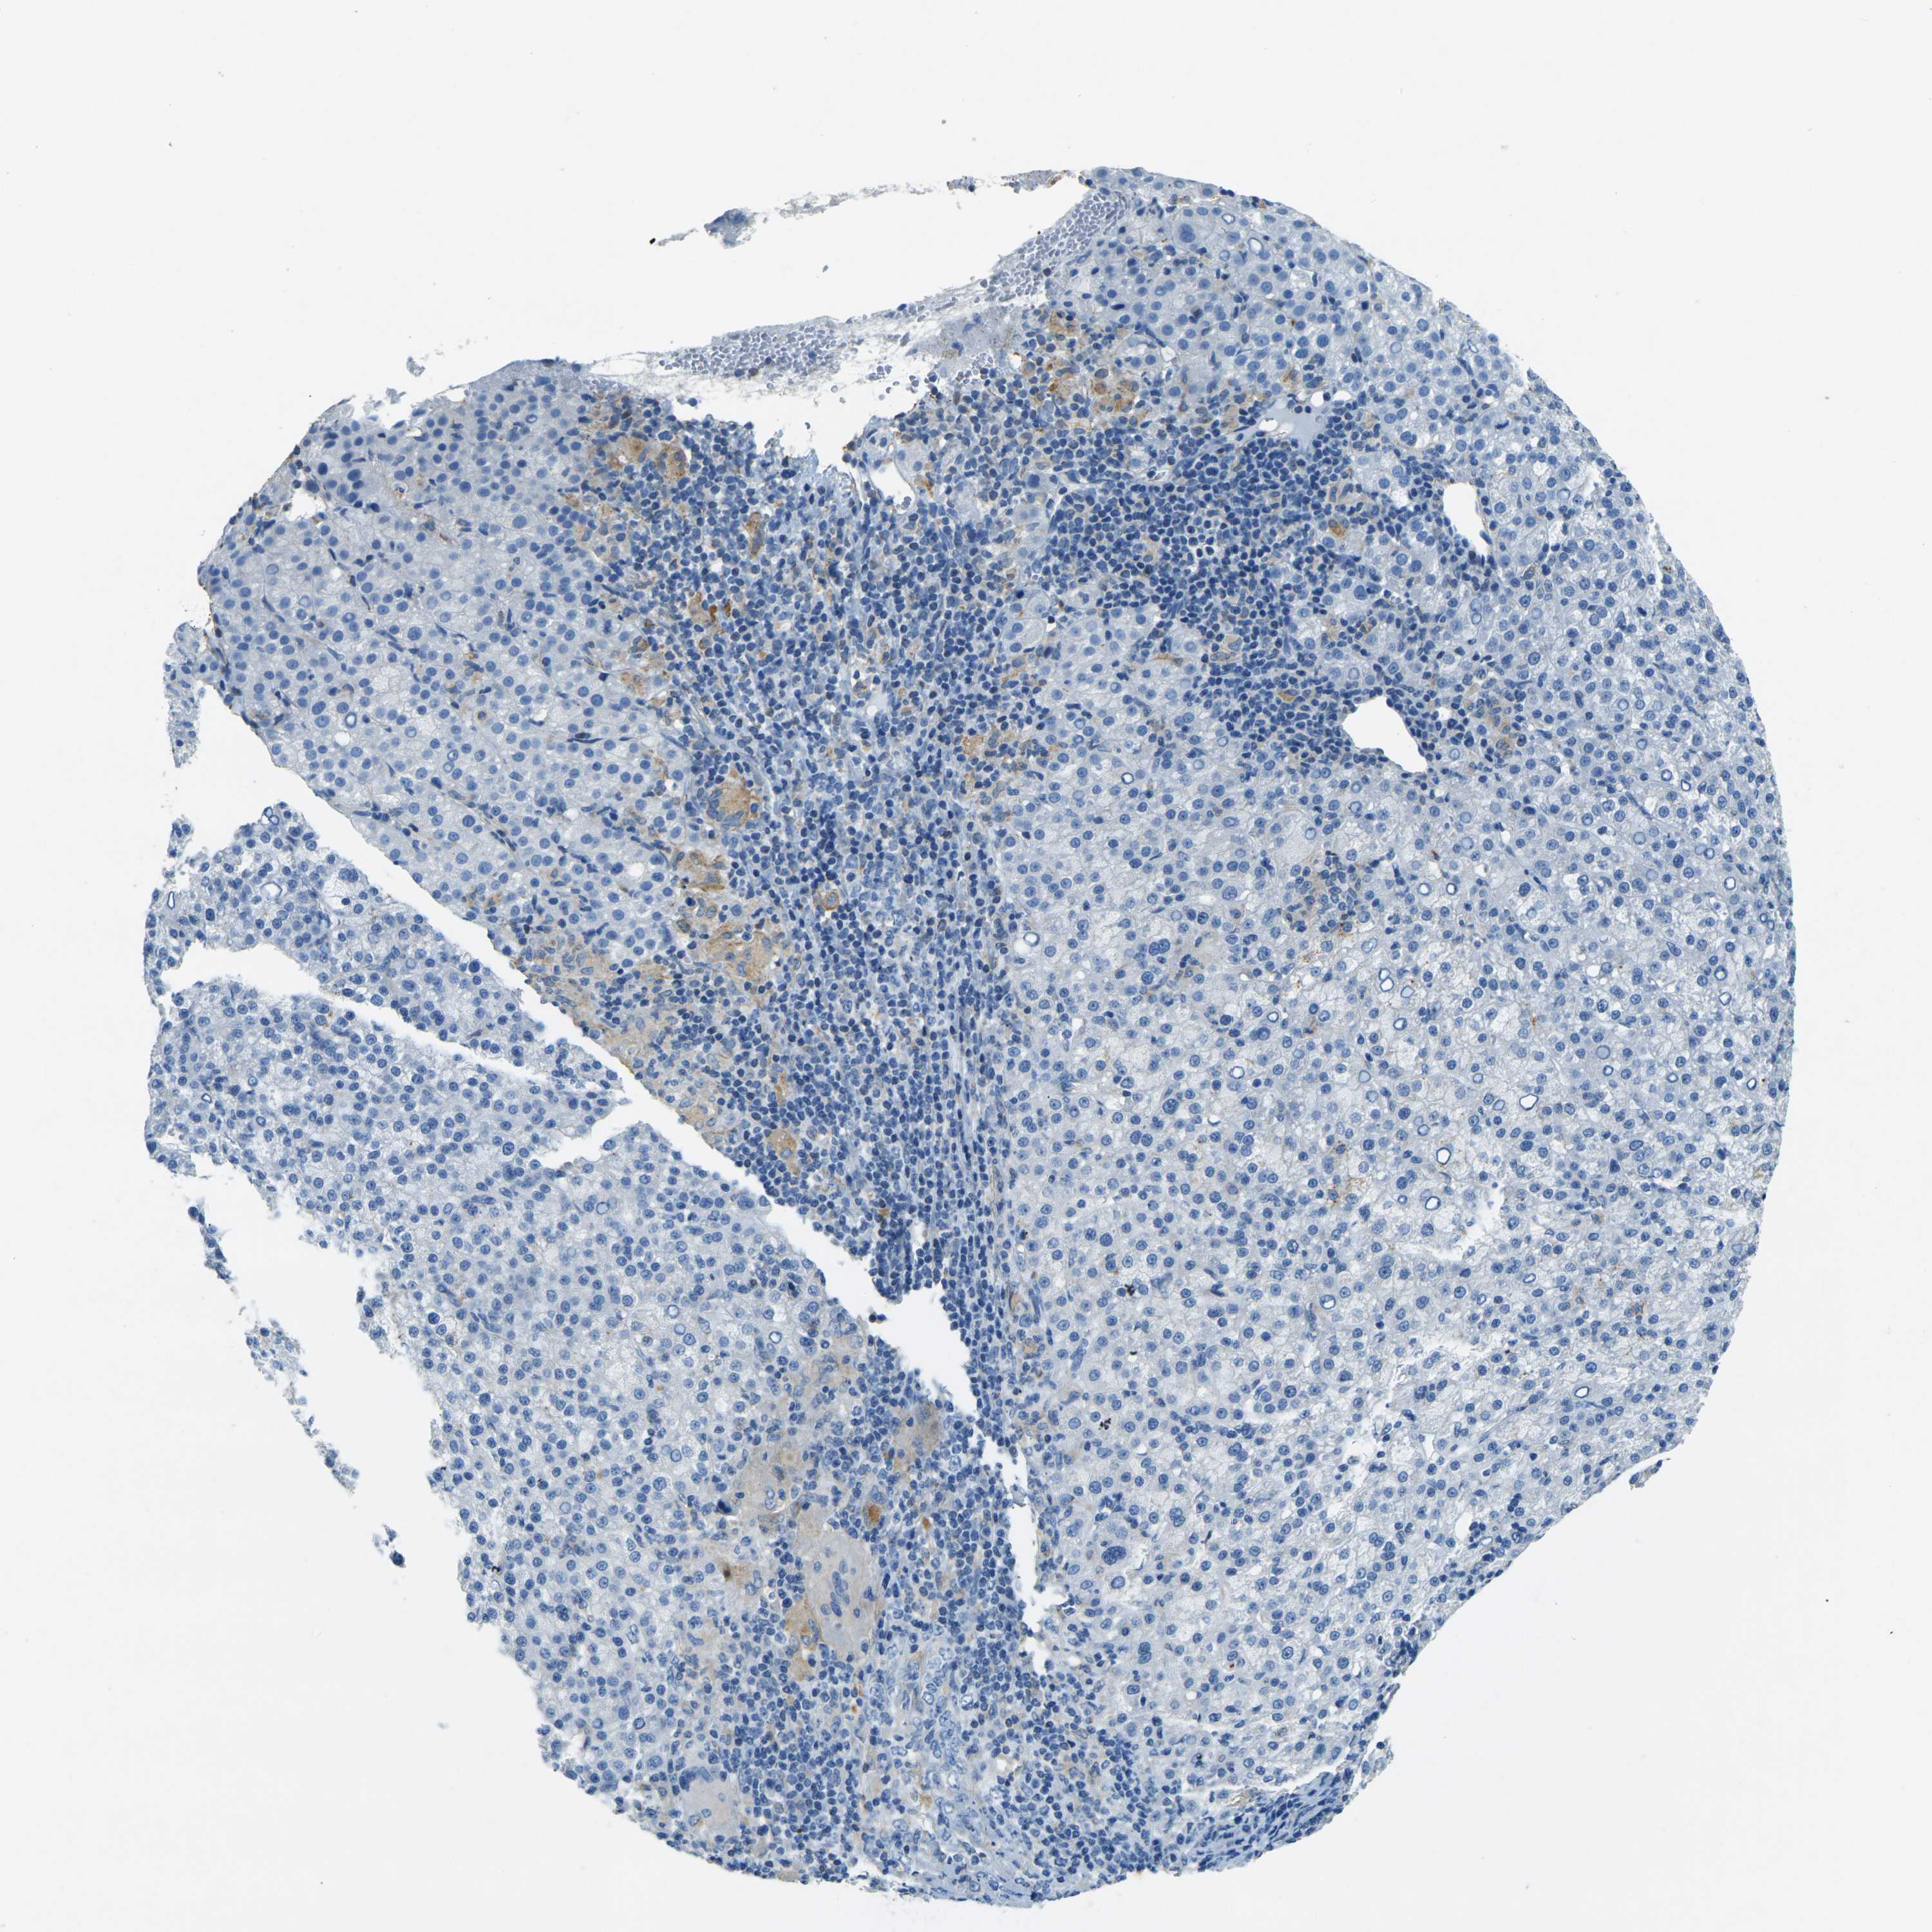

LIVER CANCER - Protein expressioni

A mouse-over function shows sample information and annotation data. Click on an image to view it in a full screen mode. Samples can be filtered based on level of antibody staining by selecting one or several of the following categories: high, medium, low and not detected. The assay and annotation is described here.

Note that samples used for immunohistochemistry by the Human Protein Atlas do not correspond to samples in the TCGA dataset.

Antibody stainingi

Antibody staining in the annotated cell types in the current human tissue is reported as not detected, low, medium, or high, based on conventional immunohistochemistry profiling in selected tissues. This score is based on the combination of the staining intensity and fraction of stained cells.

Each image is clickable and will lead to virtual microscopy that enables deeper exploration of all samples and also displays staining intensity scores, fraction scores and subcellular localization as well as patient and tissue information for each sample.

Antibody HPA006889

Antibody CAB011498

Staining

High

Medium

Low

Not detected

Intensity

Strong

Moderate

Weak

Negative

Quantity

>75%

75%-25%

<25%

None

Location

Nuclear

Cytoplasmic/membranous

Cytoplasmic/membranous,nuclear

Cholangiocarcinoma

Carcinoma, Hepatocellular, NOS